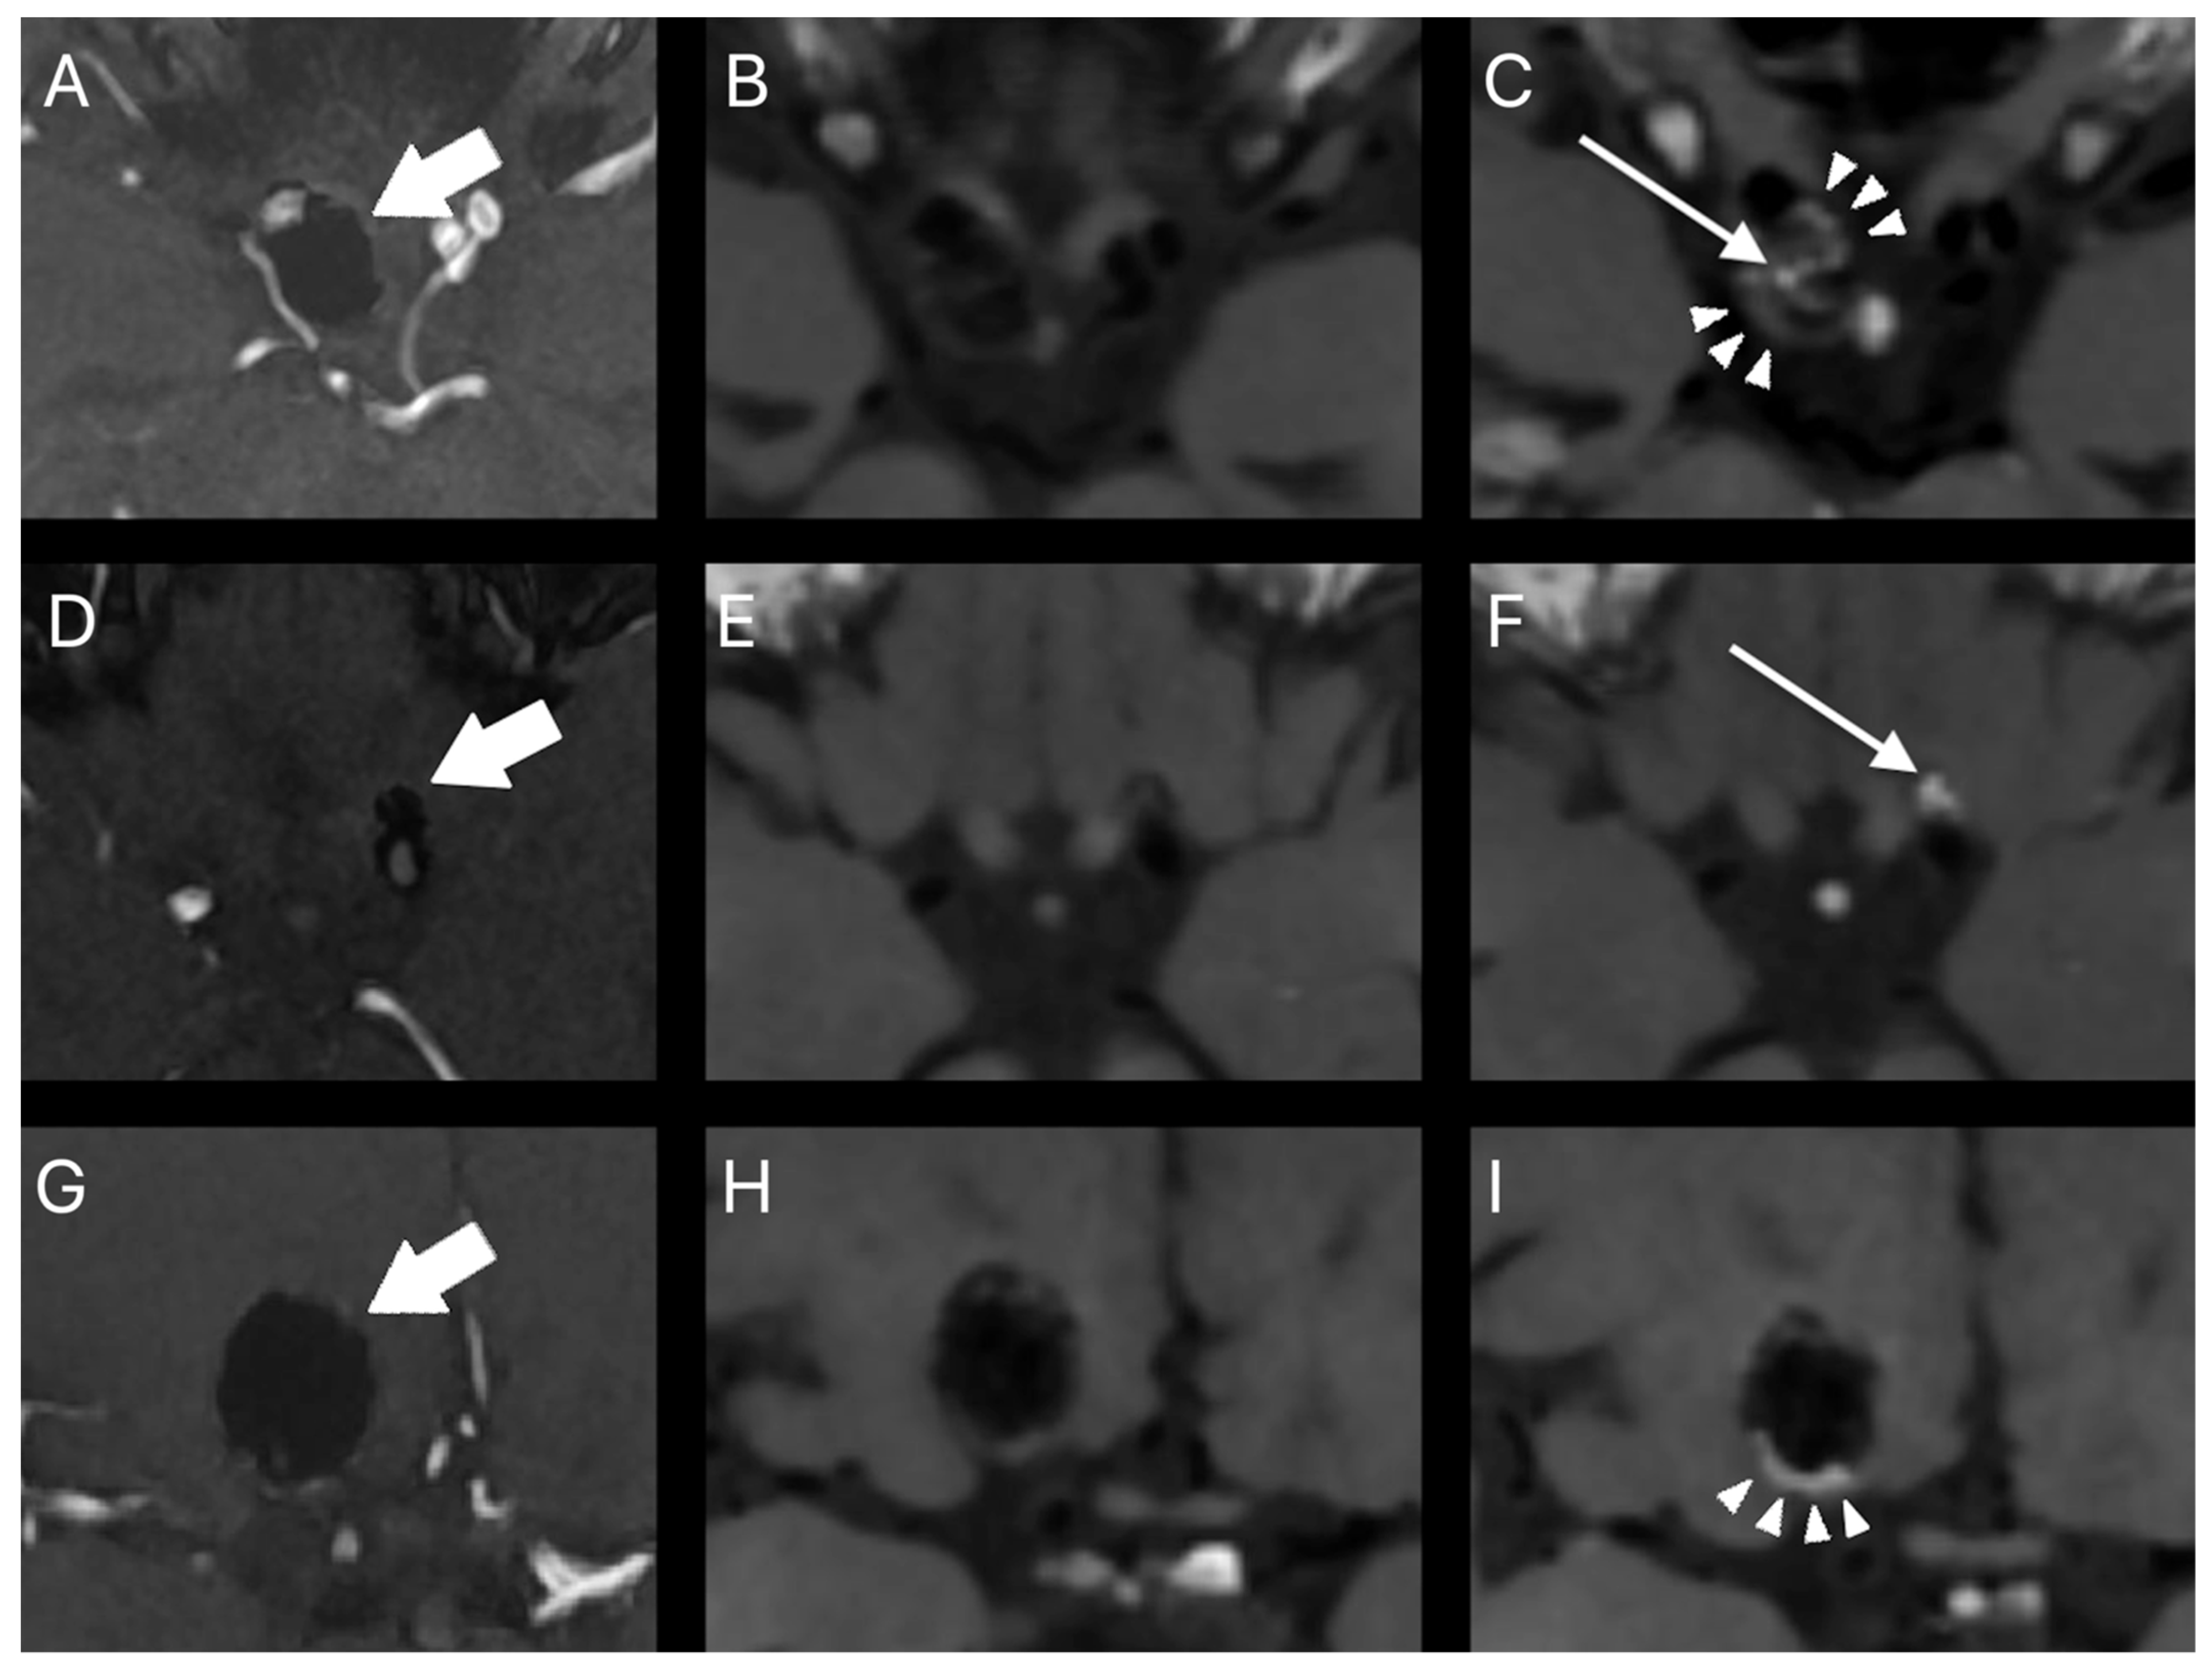

- Larsen, N.; Flüh, C.; Madjidyar, J.; Synowitz, M.; Jansen, O.; Wodarg, F. Visualization of Aneurysm Healing: Enhancement Patterns and Reperfusion in Intracranial Aneurysms after Embolization on 3T Vessel Wall MRI. Clin. Neuroradiol. 2020, 30, 811–815. [Google Scholar] [CrossRef]

- Elsheikh, S.; Urbach, H.; Meckel, S. Contrast Enhancement of Intracranial Aneurysms on 3T 3D Black-Blood MRI and Its Relationship to Aneurysm Recurrence following Endovascular Treatment. Am. J. Neuroradiol. 2020, 41, 495–500. [Google Scholar] [CrossRef]

- Songsaeng, D.; Sakarunchai, I.; Harmontree, S.; Mongkolnaowarat, S.; Charnchaowanish, P.; Zhang, S.; Krings, T. Black-blood vessel wall magnetic resonance imaging—A new imaging biomarker for regrowth of coiled saccular aneurysms? Interdiscip. Neurosurg. Adv. Tech. Case Manag. 2021, 23, 100920. [Google Scholar] [CrossRef]